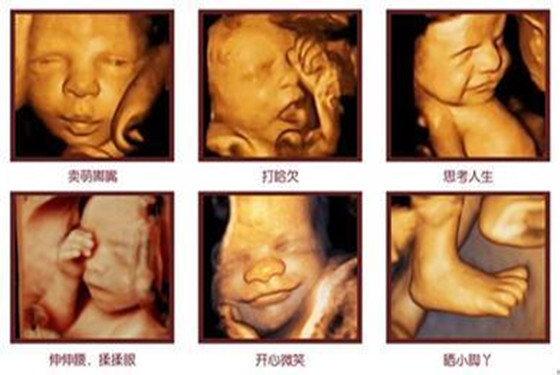

四维彩超表面成像用于产科检查,不仅可观察到胎儿成长的过程,而且能够直观地看到胎儿在母体内的活动状况,如:呼吸情况,运动情况,包括整个身体大的运动,肢体的运动,甚至是胎儿细小的吞咽动作等。医生还可以通过四维彩超来观察胎儿的张力是否良好。